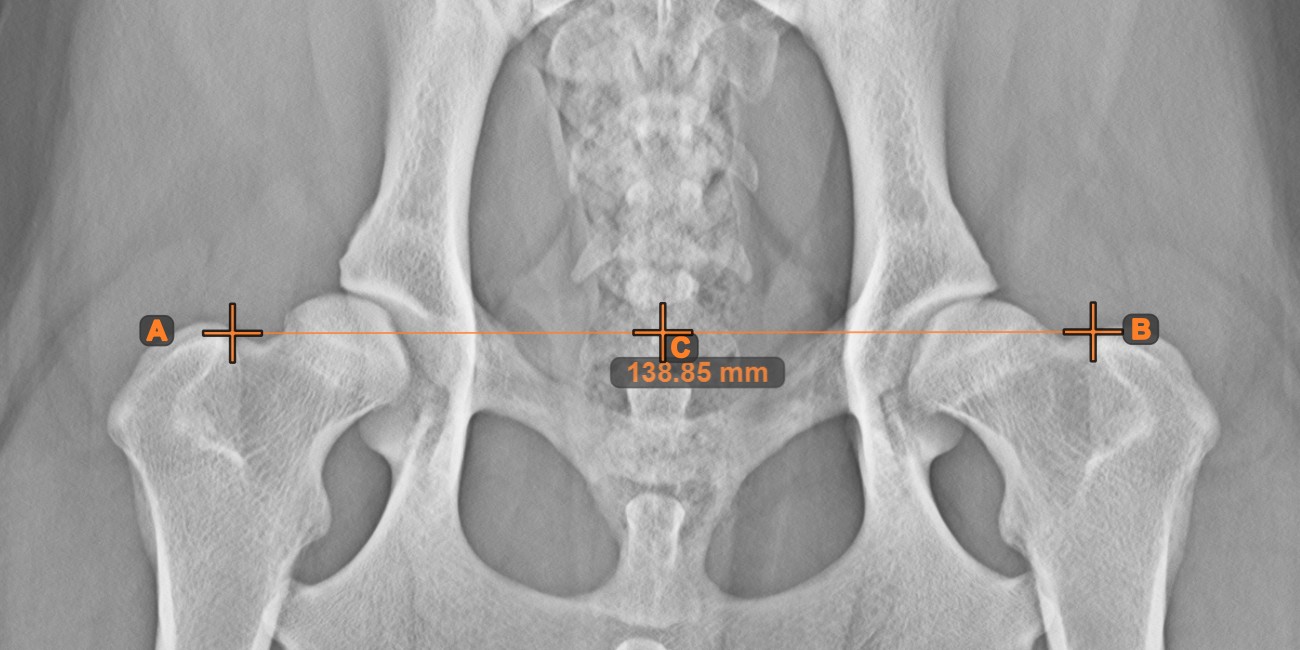

Mittlerer Punkt der Linie¶

Bestimmen und markieren Sie den Mittelpunkt einer neuen oder vorhandenen Linienmessung in der Szene mit dem Werkzeug Mittlerer Punkt der Linie.

Wählen Sie das Werkzeug aus der linken Symbolleiste aus und weisen Sie es einer der verfügbaren Maustasten zu. Setzen Sie die Start- und Endpunkte in der Szene, wählen Sie sie aus bereits vorhandenen Punkten im Bild aus oder wählen Sie eine bereits gezeichnete Linie aus der Szene. Der Mittelpunkt der Linie wird automatisch berechnet und in der Szene platziert. Der Mittelpunkt jeder Linie wird stets mit dem Buchstaben C markiert.